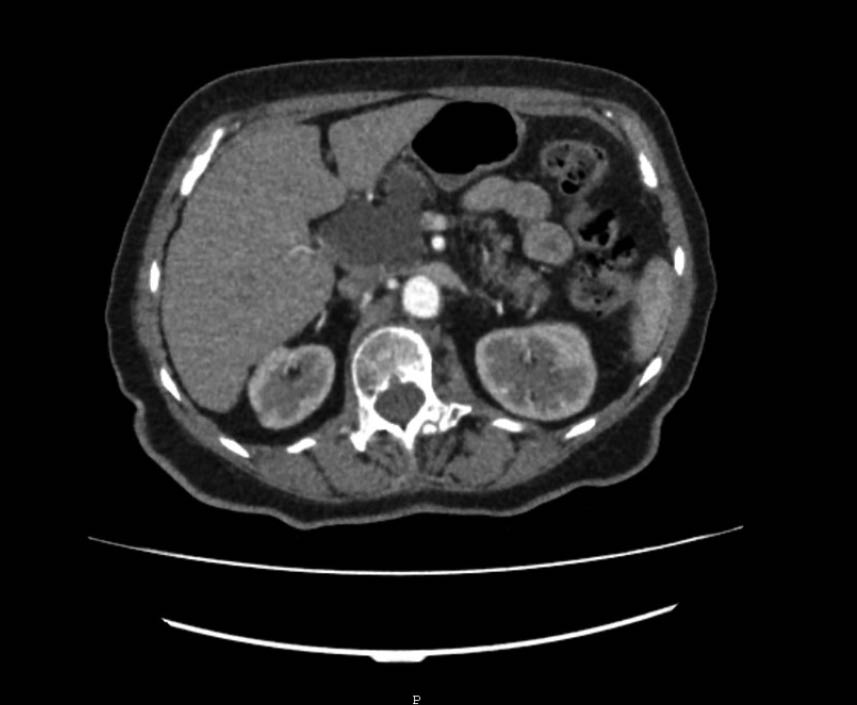

Seröses Zystadenom (SCN) – Abb. 1.A & 2.D

Muzinös-zystische Neoplasien (MCN) – Abb. 1.C & 2.A

Intraduktale papilläre muzinöse Neoplasien (IPMN) – Abb. 2.B/C & 3

IPMN sind muzinproduzierende zystische Strukturen mit Anbindung an das Pankreasgangsystem. Sie kommen in beiden Geschlechtern gleichermaßen vor, wobei die Inzidenz mit dem Alter steigt. IPMN sind die häufigsten zystischen Pankreasneoplasien und differenzieren sich je nach ihrer Lokalisation in Hauptgang-IPMN, Seitengang-IPMN und Mischtyp-IPMN. Hauptgang-IPMN und Mischtyp-IPMN zeigen in 34 – 39 % der Fälle ein invasives Wachstum und sollten daher chirurgisch reseziert werden 10,11.

Diagnostisches Vorgehen

Das ultimative Ziel bei der Diagnose und Überwachung von zystischen Neoplasien der Bauchspeicheldrüse besteht darin, zu verstehen, welche Neubildungen sich letztendlich zu bösartigen Läsionen entwickeln können. Bei der Erstdiagnose ist die MRT mit MRCP die sensitivste Schnittbildgebung zur korrekten Beurteilung einer zystischen Neoplasie des Pankreas. Damit kann die Kommunikation zwischen einer Läsion und dem Pankreasgangsystem am besten beurteilt werden, ebenso wie das Vorhandensein eines randständigen Knotens. Darüber hinaus ist die MRT/MRCP sehr empfindlich, um festzustellen, ob ein(e) PatientIn einzelne oder multifokale Zysten aufweist 4.

Wenn nach einer CT- und/oder MRT-Untersuchung keine eindeutige Diagnose vorliegt, sollte eine EUS durchgeführt werden. Obwohl diese Untersuchung stark von der Erfahrung des Untersuchers abhängt, ist sie hilfreich zur Unterscheidung zwischen muzinösen und nichtmuzinösen Zysten sowie zur Bewertung von worrisome features und high-risk stigmata (Tab. 1), die auf eine Malignität hinweisen können 18. Zur Beurteilung von randständigen Knoten ist die Kontrast-EUS die bevorzugte Technik. Falls weiterhin Zweifel bestehen, ist die Feinnadelaspiration (FNA) zur Analyse der Zystenflüssigkeit notwendig, sofern dies technisch machbar ist. Die Analyse der Zystenflüssigkeit kann zur Identifizierung des Zystentyps verwendet werden. Dabei sind erhöhte CEA-Werte bei muzin-produzierenden Zysten mit einer Genauigkeit von 79 % verbunden, während erhöhte Amylasewerte eine Spezifität von über 90 % für eine Pseudozyste aufweisen 19.